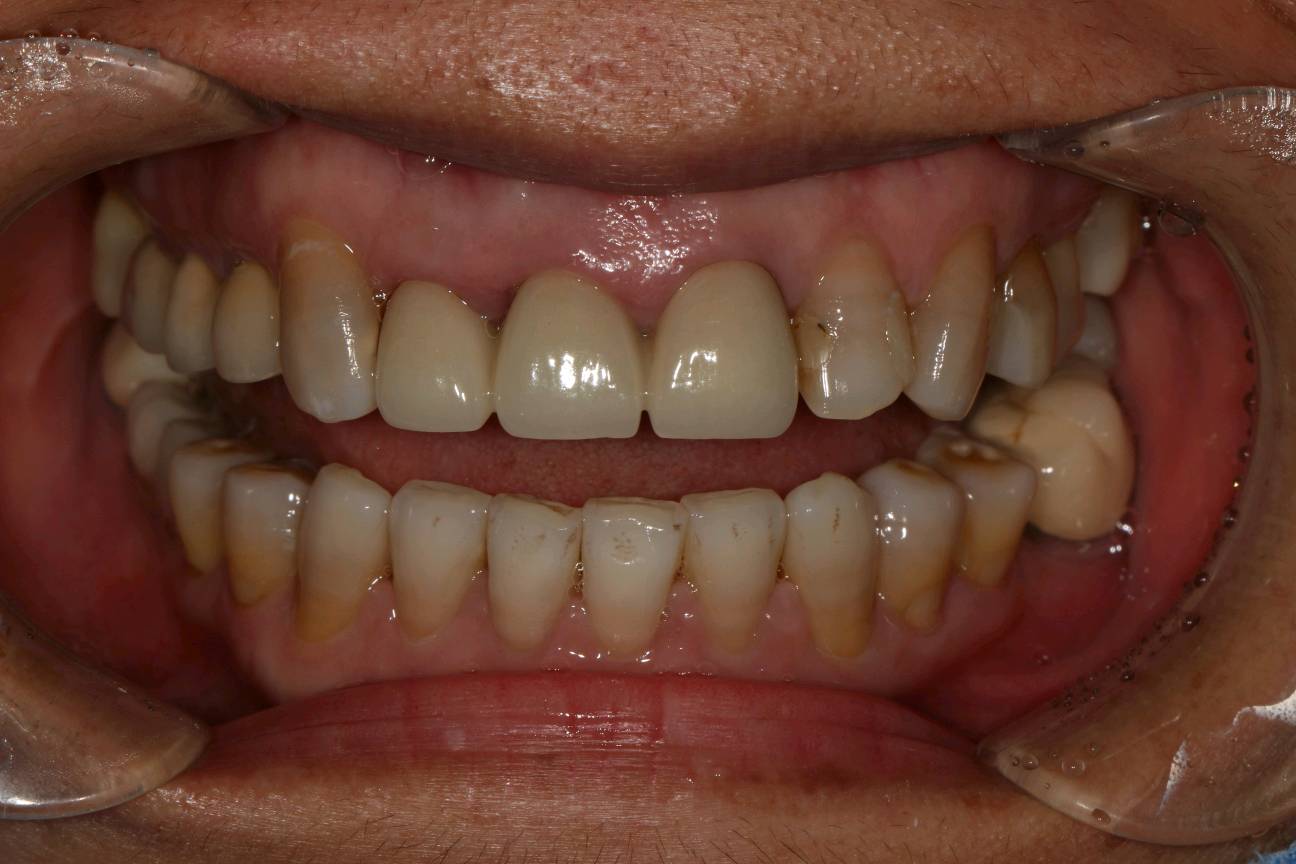

患者女,四十岁,前牙松动一个月。口内检查:12,11,21连冠修复,松动(+++),12冠根折。X线显示:骨密度良好,牙槽骨骨量不足。治疗计划:拔除+植人骨粉骨膜+种植修复。

术前